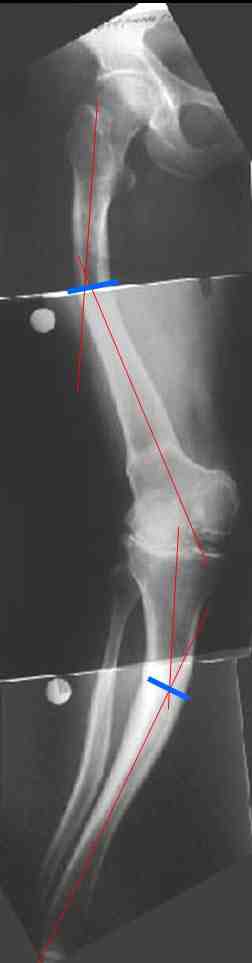

В данном случае перед эндопротезированием мы бы корригировали оси бедренной и большеберцовой костей (см. вложение). Дистальный эпидиафизарный угол бедра будет корригирован при эндопротезировании. Тип остеотомии и коррекции деформации (клиновидная резекция - одномоментная коррекция; формироване треугольных или трапециевидных регенератов во времени) - исходя из

относительной длины конечности.